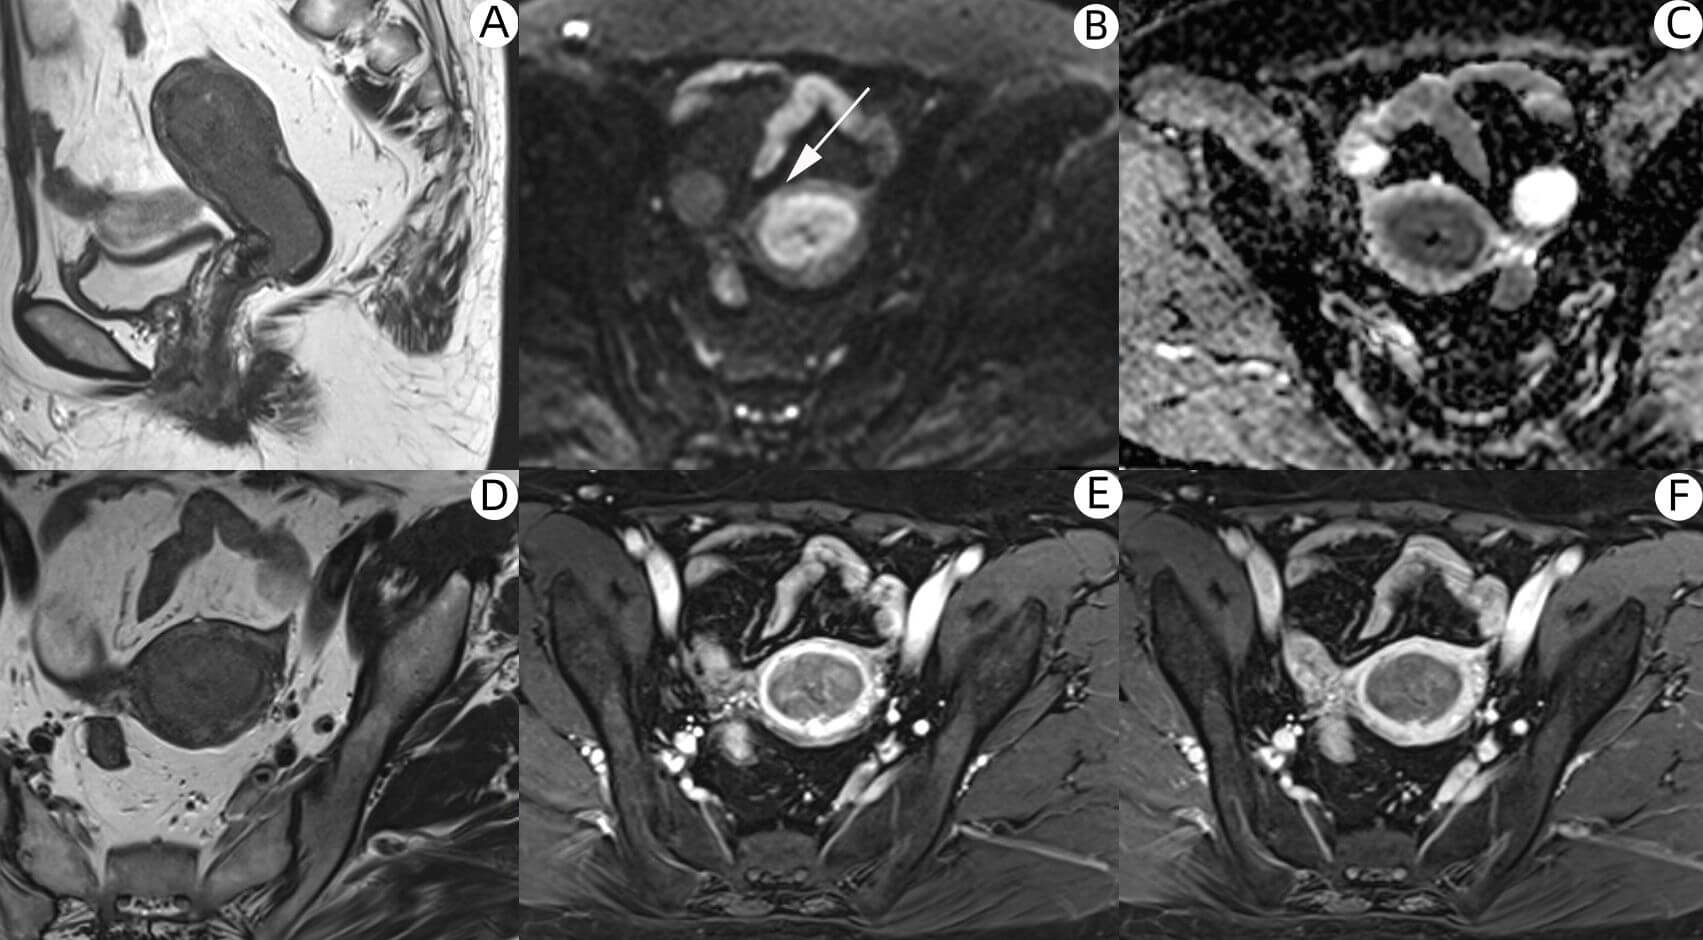

Wang et al. [16] conducted a meta-analysis of 19 studies involving 961 patients, which showed that in a subgroup of 7 studies, the AUCs of DWI combined with T2WI and DCE combined with T2WI for diagnosing DMI in EC were 0.959 (95% confidence interval [CI]: 0.932–0.986) and 0.929 (95% CI: 0.847–1.000), respectively, with no statistically significant difference between the two. The study further indicated that the use of DWI alone, DCE alone, or the combination of DWI and DCE were all reasonable approaches for diagnosing DMI. In addition, sensitivity analysis suggested that DWI may be more sensitive than DCE in detecting DMI. This conclusion is consistent with our findings. To corroborate this, we present a representative case from our study (Fig. 3), illustrating the potential advantage of DWI in identifying DMI. Based on our results and previous studies, individualized MRI protocols without DCE are feasible, offering advantages such as avoiding contrast agents, reduced invasiveness, lower cost, shorter acquisition time, and maintenance of diagnostic reliability for DMI.

Fig. 3.

In a 54-year-old patient with EC, postoperative pathology confirmed the presence of DMI. (A) Sagittal T2WI of the uterine body. (B–F) Axial images of the uterine body: (B) DWI (b = 800), (C) ADC_map, (D) T2WI, (E) early-phase, and (F) late-phase DCE images. Fig. 3B showed DMI of the anterior wall of the uterine corpus with a high signal area (as indicated by the white arrows). The corresponding ADC_map showed a slightly low signal shadow. However, the dynamic enhancement scans of early and late images did not show DMI. EC, endometrial cancer.